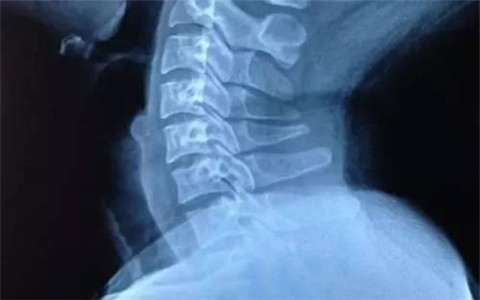

頸椎病是指各種因素引起頸椎結(jié)構(gòu)發(fā)生改變,造成與頸椎相關(guān)聯(lián)的脊髓、神經(jīng)根、動(dòng)脈血管、韌帶等組織出現(xiàn)損傷或功能障礙,從而引發(fā)一系列的臨床癥狀的疾病,是中老年人的常見病、多發(fā)病。由于頸椎病來(lái)自于不同組織和器官的損傷,特別是頸椎間盤的病變,使頸椎病的臨床表現(xiàn)多種多樣,所以醫(yī)生們將這些臨床表現(xiàn)稱為綜合征,因此頸椎病也稱作頸椎綜合征。

頸椎病是什么狀態(tài),怎么改善?(圖)_1

頸椎病癥狀

1、頸型頸椎?。夯颊叱霈F(xiàn)頸部強(qiáng)直、疼痛、肩背疼痛發(fā)僵;點(diǎn)頭、仰頭及轉(zhuǎn)頭活動(dòng)受限;有時(shí)也會(huì)出現(xiàn)頭暈的癥狀。

2、椎動(dòng)脈型頸椎病:由于椎動(dòng)脈受到壓迫或刺激,引起功能失調(diào)、腦部供血不足而產(chǎn)生的一系列癥狀?;颊叱霈F(xiàn)發(fā)作性眩暈,伴有惡心、嘔吐、耳鳴或聽力下降、下肢突然無(wú)力而猝倒,這些癥狀與頸部位置改變有直接的關(guān)系。

3、神經(jīng)根型頸椎病:發(fā)病率最高,早期癥狀為頸痛和頸部發(fā)僵,患者不同程度地存在頸、肩、背、上肢及手部的疼痛,夜間疼痛更厲害;少數(shù)為燒灼痛,疼痛程度時(shí)輕時(shí)重;患側(cè)上肢感覺沉重、握力減退,有時(shí)出現(xiàn)持物墜落。

頸椎病是什么狀態(tài),怎么改善?(圖)_2

4、脊髓型頸椎病:脊髓受到刺激、壓迫,使血液供應(yīng)不足,導(dǎo)致脊髓功能障礙,出現(xiàn)下肢麻木、沉重、行走困難,有踩棉花感;上肢麻木、疼痛,雙手無(wú)力、不靈活,持物易落;軀干部出現(xiàn)感覺異常,患者常感覺在胸部、腹部、或雙下肢有如皮帶樣的捆綁的感覺。

5、交感神經(jīng)型頸椎病:因頸部交感神經(jīng)受壓產(chǎn)生癥狀。患者表現(xiàn)為頭痛或偏頭痛、頭暈、惡心、嘔吐、視物模糊、視力下降、眼睛后部脹痛、心跳加速、頭頸部以及四肢出汗異常以及聽力下降,發(fā)音障礙等;也可出現(xiàn)眼花、流淚、鼻塞、心動(dòng)過(guò)緩、胃腸脹氣等復(fù)雜的表現(xiàn)。

6、混合型頸椎?。荷鲜鰞煞N或兩種以上類型癥狀同時(shí)出現(xiàn)便稱為混合型頸椎病。

頸椎病發(fā)病時(shí)往往不是單一類型,而經(jīng)常是兩種或兩種以上類型同時(shí)出現(xiàn)。如果病情進(jìn)一步發(fā)展,還會(huì)引起大腦供血不足、腦功能減退、極少數(shù)病情嚴(yán)重的患者可能會(huì)引起下肢運(yùn)動(dòng)功能障礙甚至癱瘓。